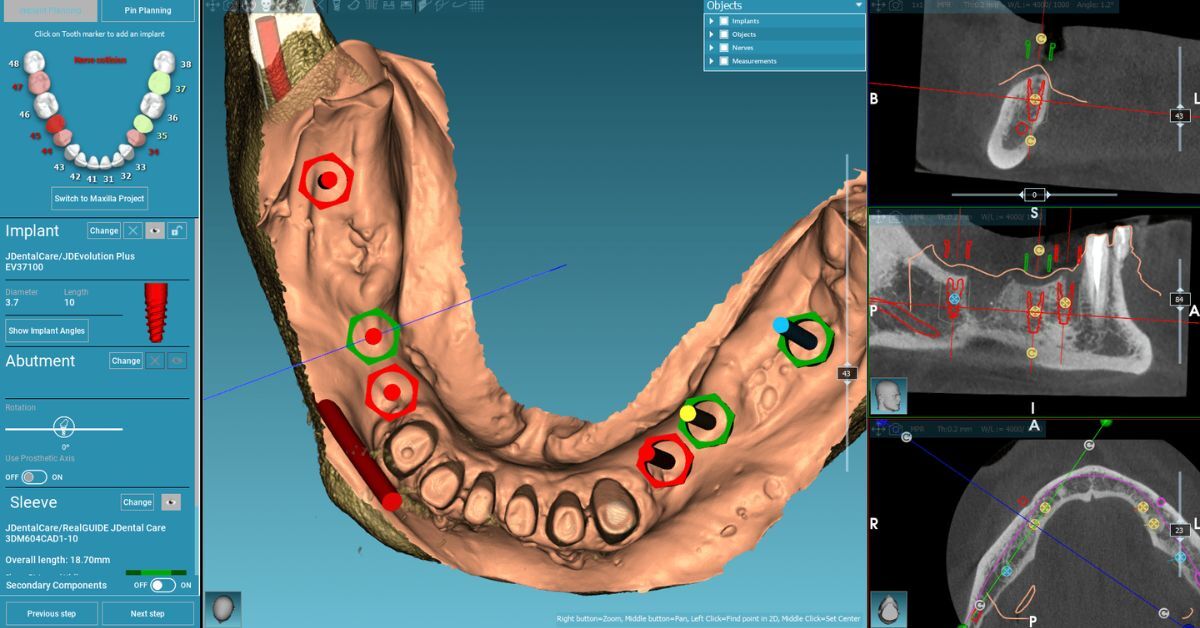

Digital Implant Planning: using the 3D scan data, we plan the ideal implant position, size, and angle – ensuring maximum stability and natural aesthetics.

3D CBCT Scan: this is where precision begins. The scan provides detailed information about bone thickness, density, and the exact position of key anatomical structures such as nerves and sinuses.